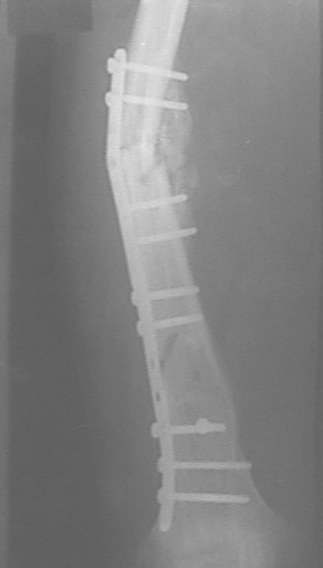

При невозможности или чрезмерной травматичности одномоментного восстановления длины можно пойти двухэтапно (аппарат, потом гвоздь). Похожий пример см. тут. Прошло уже года полтора после остеосинтеза. Может, коллега Зырянов покажет годичный результат, если есть?

Отправитель: Сергей Зырянов 16 Декабрь 2005, 08:20

Александр Николаевич, к сожалению больной не является на контрольные осмотры. Я последний раз видел больного, когда прошло 7 месяцев после операции БОС. У него все хорошо. Каких либо жалоб и ограничений в нагрузке нет. Высылаю снимки до операции и последние снимки.